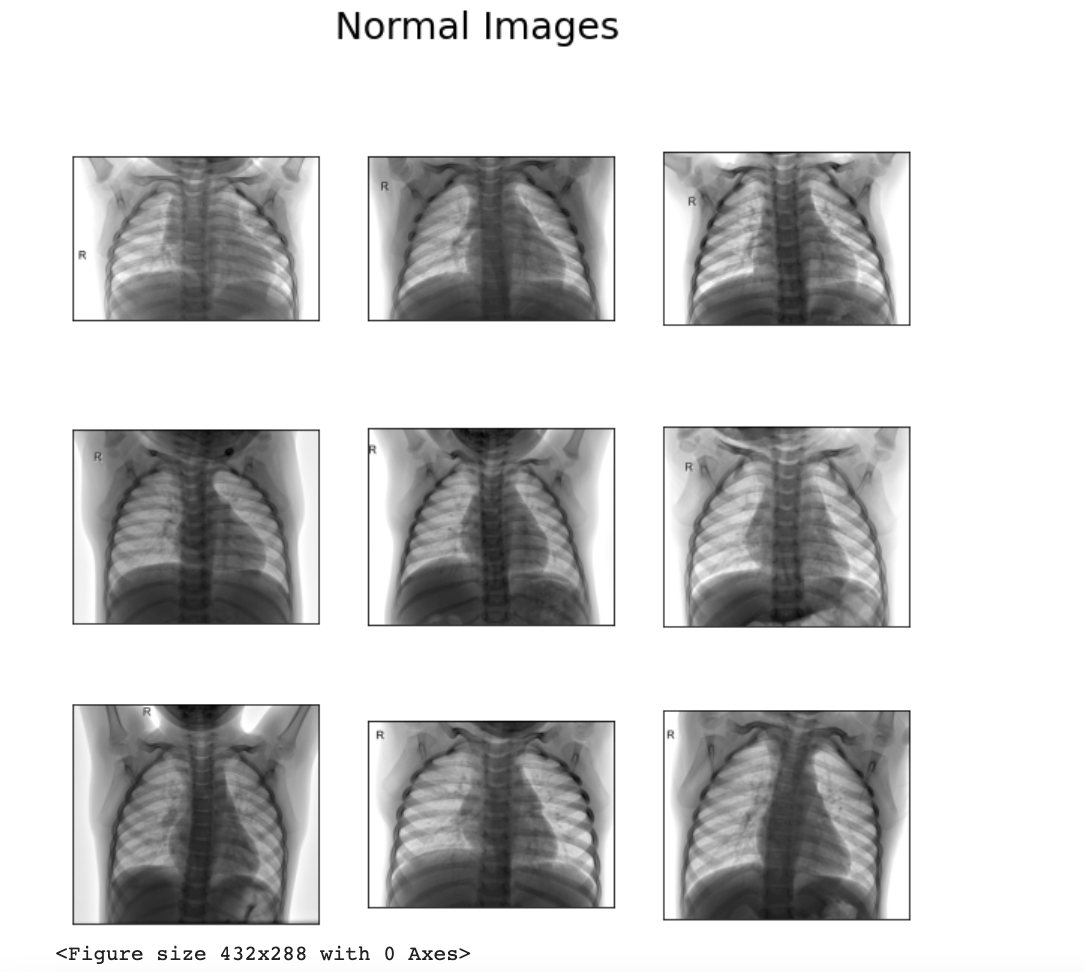

Dr. Machine Can it Diagnose COVID19? by Amulya Saridey Towards